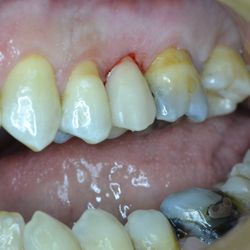

Η νεαρή αυτή ασθενής προσήλθε στο ιατρείο με κάταγμα του παρειακού φύματος του άνω αριστερού προγομφίου.

Το δόντι είχε υποστεί απονεύρωση. Προκειμένου να διαφυλαχθεί η δομική ακεραιότητα του υπολοίπου δοντιού, αποφασίστηκε να αποκατασταθεί το δόντι με εργαστηριακή επένθετη έμφραξη σύνθετης ρητίνης με ελάχιστη αποκοπή οδοντικής ουσίας.

Διατηρήθηκε έτσι ακέραιο το δόντι ενώ η αισθητική του αποκαταστάθηκε απόλυτα.